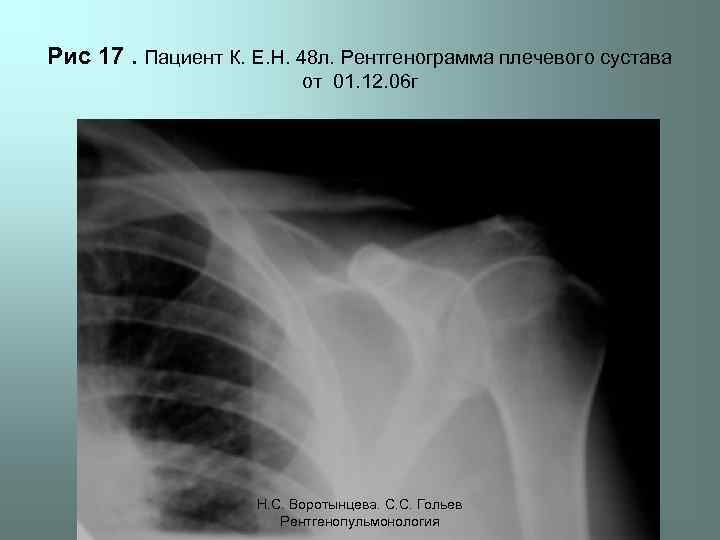

Рис 17. Пациент К. Е. Н. 48 л. Рентгенограмма плечевого сустава от 01. 12. 06 г Н. С. Воротынцева. С. С. Гольев Рентгенопульмонология